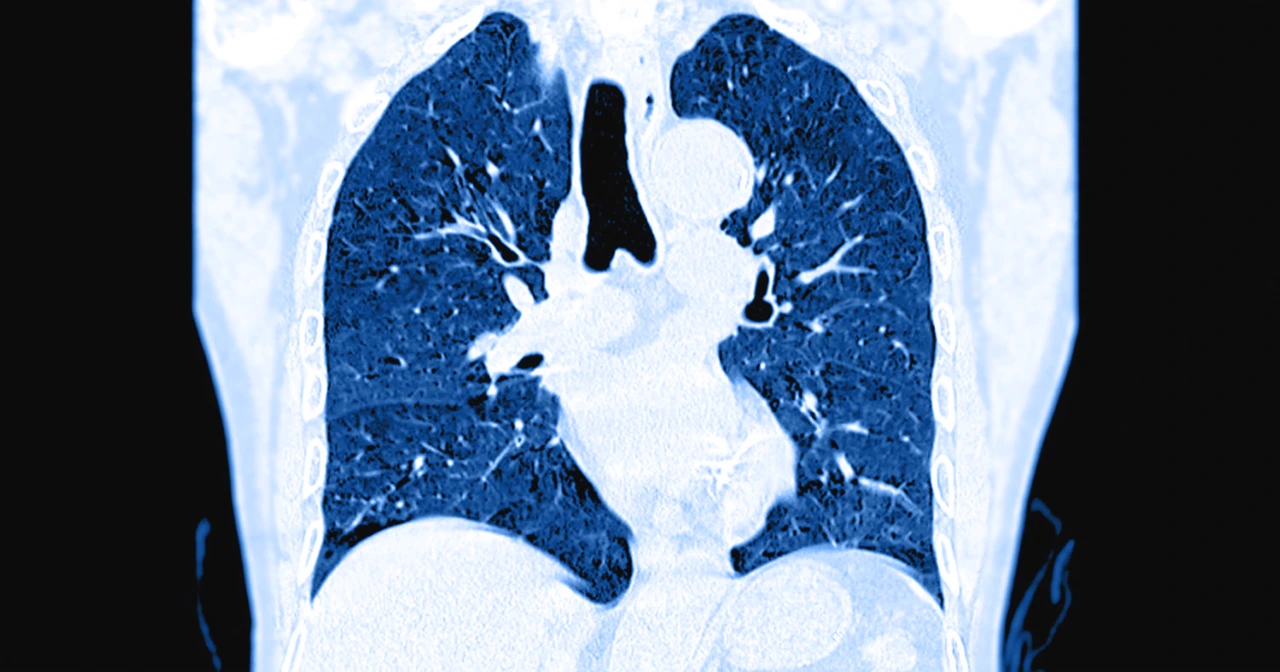

Dentro de las herramientas de imagen que se emplean con mayor frecuencia está la tomografía computarizada con angiografía o angio-TAC, que es el método de referencia para visualizar los coágulos en las arterias pulmonares.

TAC de un paciente, como procedimiento diagnóstico para identificar si ha desarrollado una embolia pulmonar.